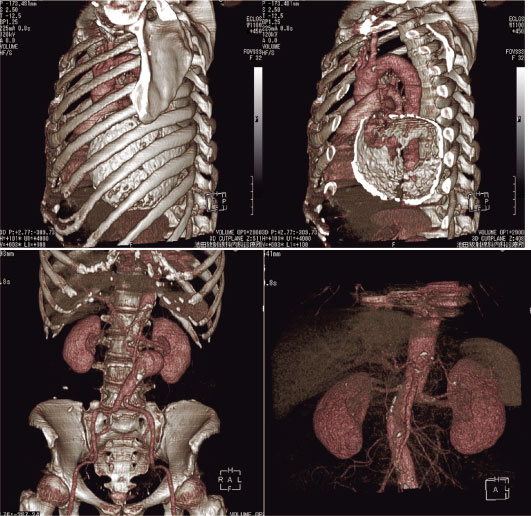

以来,MD-CTの導入までは10年かかった。経済的な余裕ができたためではない(ありえない)。普及によるMD-CTの低価格化と冒頭のような事情からである。検査時間は短くPCへの転送までの時間も大幅に短縮された。計画・撮像は自分で行い,画像処理から説明までもリアルタイムで患者とPCを見ながら行える。画像処理内容もいくつか追加されている。感激した。多くの新しい高機能機種に触れられる環境にあるドクターや,研修医や学生からみれば「今頃なにを」と思われるかもしれない。浦島太郎で結構。とにかく再び『三次元診断』が身近となった環境を10年ぶりに味わえることが楽しい。以下,導入3カ月間に収集した三次元画像のいくつかを供覧する。

画像 4 上段は被包石灰化した嚢胞。右は切削像。下段左,腹部大動脈瘤。

右膵臓癌(脾動脈に著明な広狭不整を認める)。